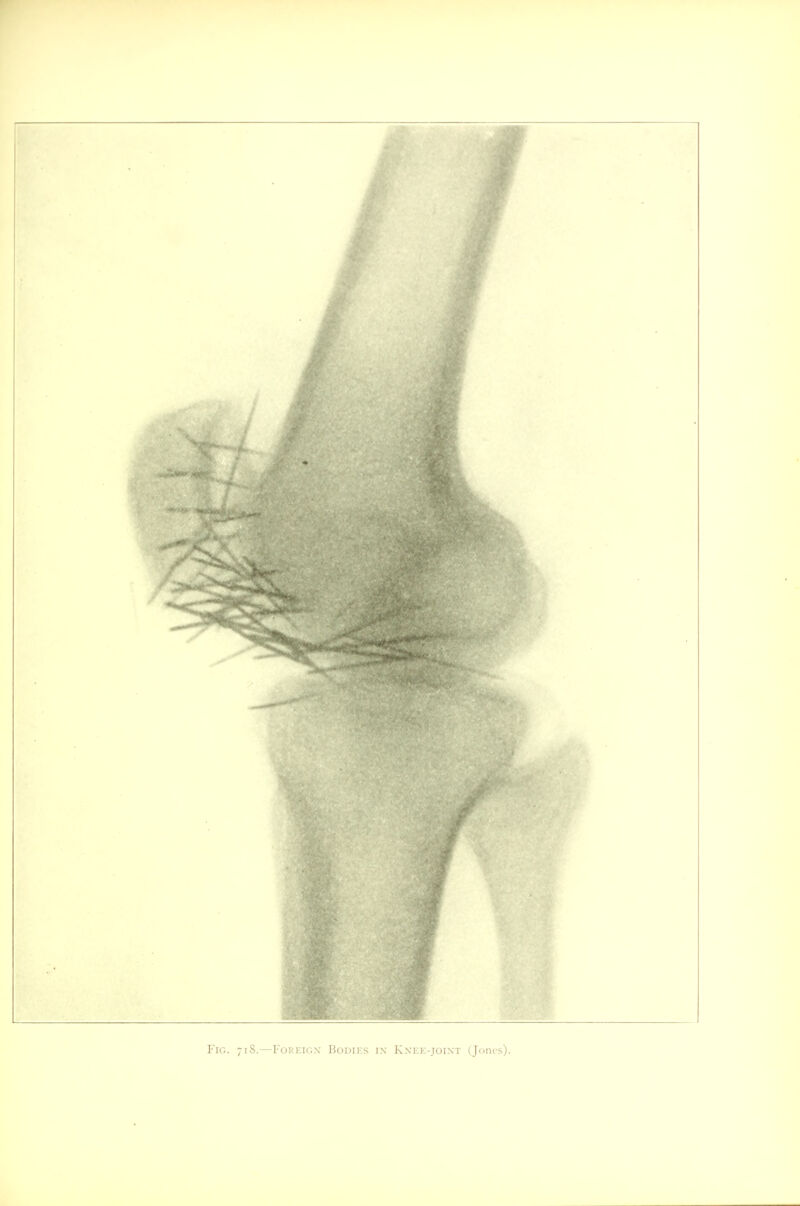

935/968 (page 915)